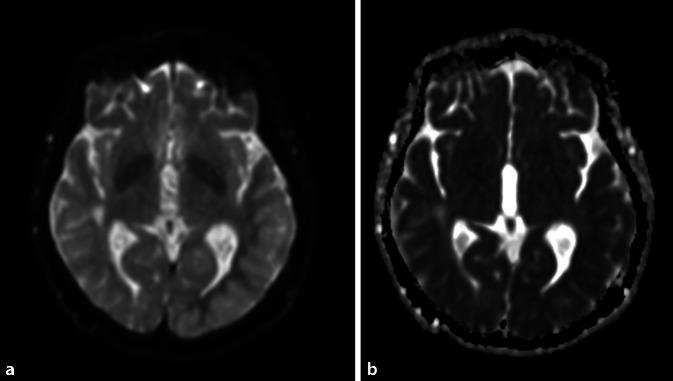

Nervenarzt. 2023 Feb;94(2):145-148. doi: 10.1007/s00115-022-01413-z. Epub 2022 Dec 9.